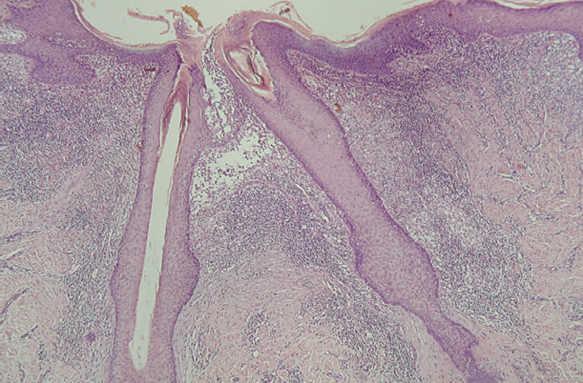

En la HCL el infiltrado se localiza normalmente en la dermis adventicial, y puede invadir la epidermis, produciendo clínicamente lesiones erosivas (figs. 13 y 14). En las formas nodulares puede invadir la hipodermis. En pacientes adultos se ha descrito la distribución del infiltrado alrededor de los anejos (figs. 15 y 16) 13. Aparecen otras células inflamatorias en número variable, sobre todo neutrófilos, eosinófilos, linfocitos y mastocitos y, en menor medida, células gigantes multinucleadas. De forma clásica se han descrito tres subtipos principales: proliferativo, granulomatoso y xantomatoso, que se intentan correlacionar con las diferentes formas clínicas. Histológicamente no existen diferencias entre la HCL y la reticulohistiocitosis congénita autoinvolutiva 7.

Fig. 15.--Infiltrado de células de Langerhans rodeando los folículos pilosos. (Hematoxilina-eosina, x10.)

Fig. 16.--Detalle del infiltrado rodeando los anejos. (Hematoxilina-eosina, x20.)